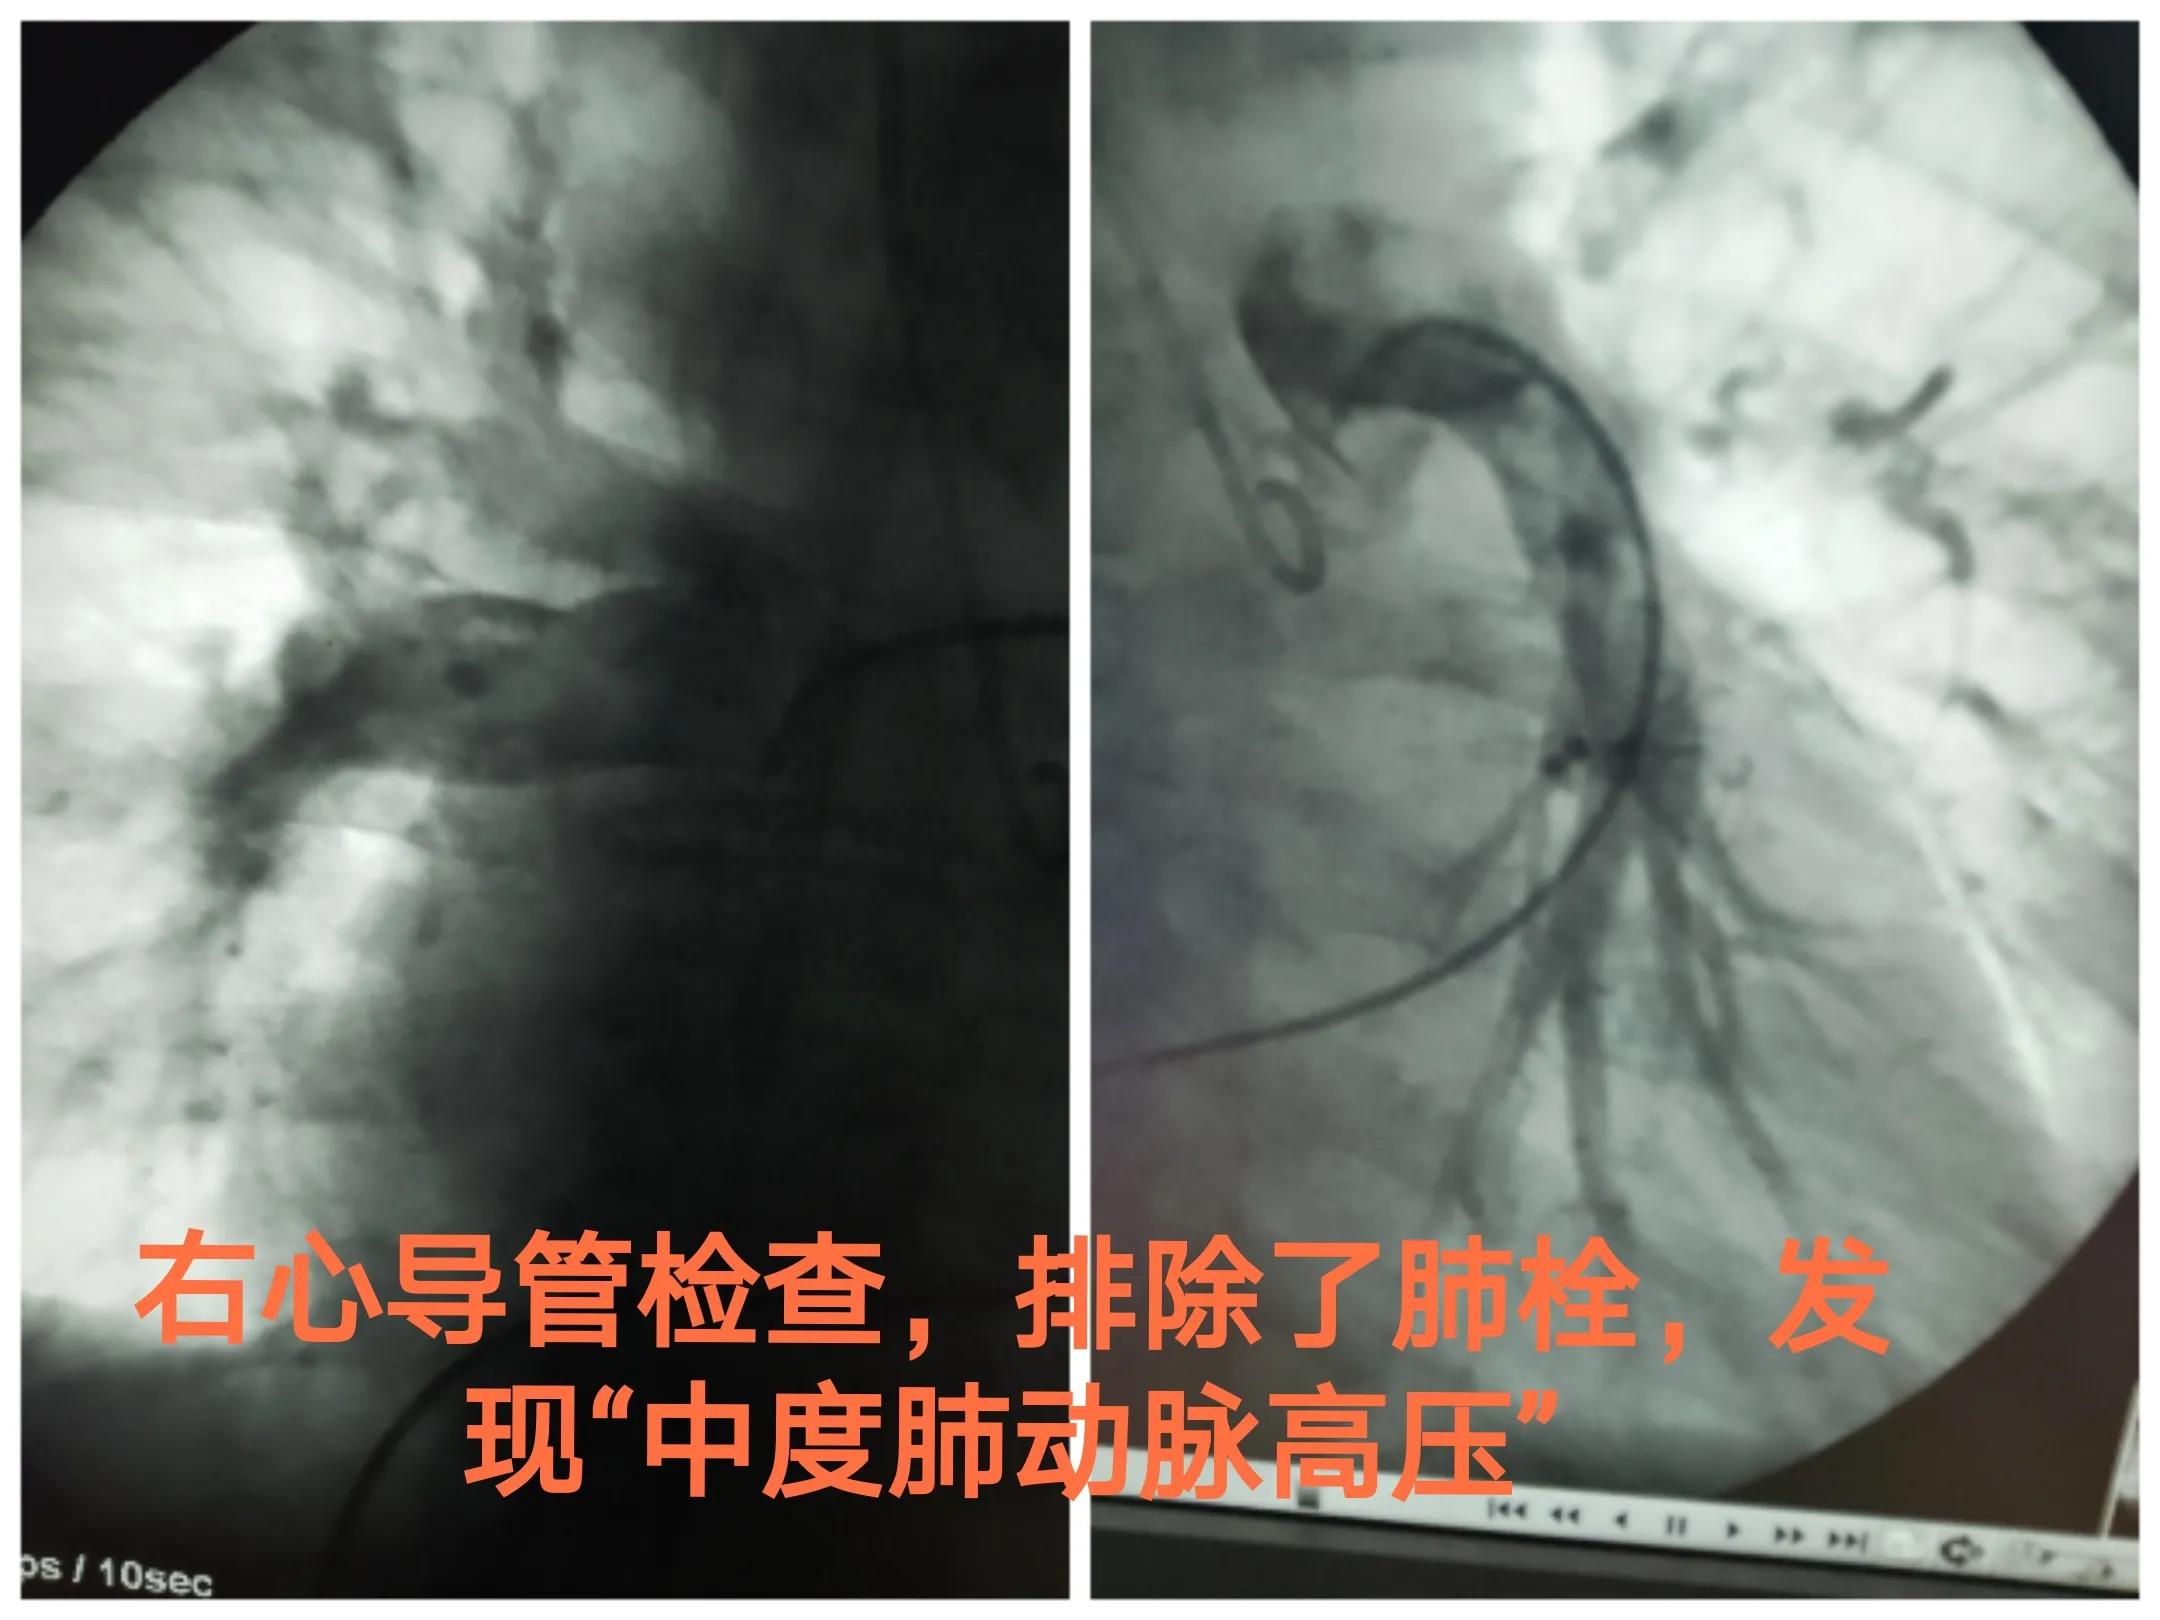

做了右心功能检查,发现确实肺动脉、右心室、右心房压力升高,另外排除了明显的肺栓塞。